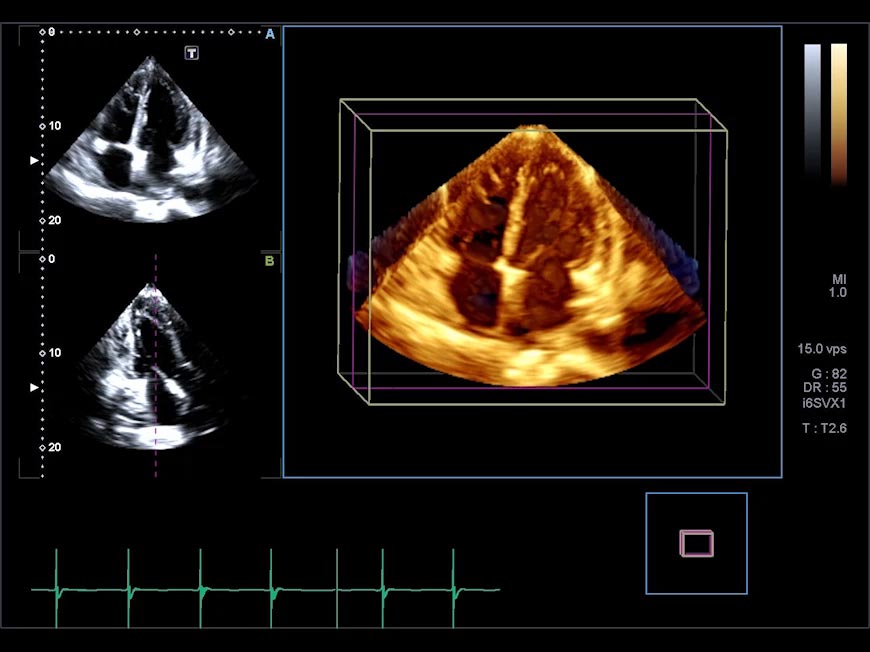

Small compact, lightweight design.

Cardiac Volume Matrix Transducer* (i6SVX1)

- Matrix array

- Single crystal

- Advanced volume features

- Freq: 1.8-5.2 MHz

- Application:

3D Cardiac (adult heart)

*Available on the Aplio i900 only.

4D volume imaging for routine clinical use.

4D-TEE / Volume Matrix Transducer* (i6SVX2)

The Aplio i-series volume matrix transducer enables you to acquire high-quality 4D volumes at high frame rate. A host of advanced analysis tools allows for in-depth assessment of cardiac anatomy and function.

*Available on the Aplio i900 only.